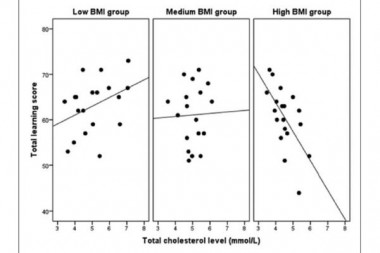

The objective of this study was to examine the relationship between verbal memory and total cholesterol (TC) levels related to body mass index (BMI) in healthy young women.

The objective of this study was to examine the relationship between verbal memory and total cholesterol (TC) levels related to body mass index (BMI) in healthy young women.